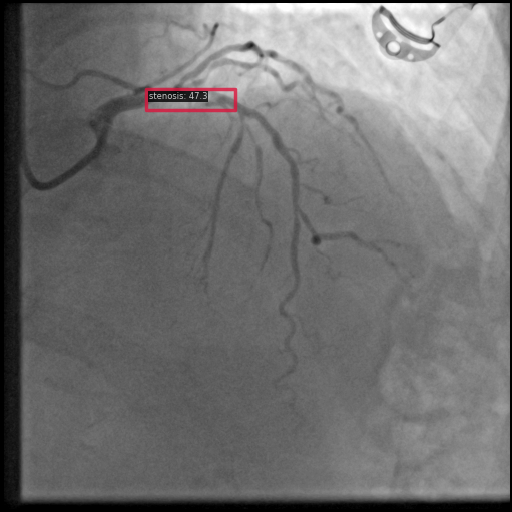

Figure 1 shows sample images from the ARCADE dataset with annotations for stenosis detection. The annotations highlight regions of arterial narrowing, providing ground truth data for training and evaluating object detection models.

To further assess the detection performance, qualitative results for three test images are presented in Figure 2. The first column shows the original images with ground truth annotations. The second, third, and fourth columns depict detections from DINO-DETR, Grounding DINO, and YOLO, respectively.

(a) Original (b) DINO-DETR (c) Grounding DINO (d) YOLO

The qualitative comparison in Figure 2 reinforces the trends observed in the quantitative evaluation. DINO-DETR produced fewer detections, occasionally missing relevant stenotic regions, consistent with its conservative detection strategy aimed at minimizing false positives [6]. Grounding DINO, although capable of identifying more regions, sometimes resulted in cluttered predictions due to over-detections [7]. YOLO provided a reasonable trade-off by effectively capturing anatomical structures while maintaining relatively high confidence scores and clear visualizations [5].